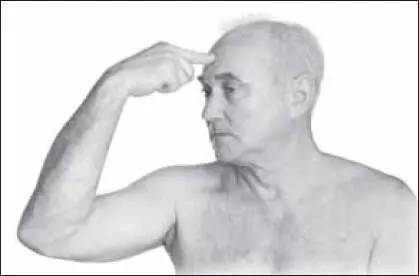

Надо начинать с точки э-чжун (на 1,5 цуня выше точки инъ-тан, которая находится между бровями, на средней линии лица) (рис. 124).

Массирующий палец фиксируют на точке, располагая его перпендикулярно к области лба.